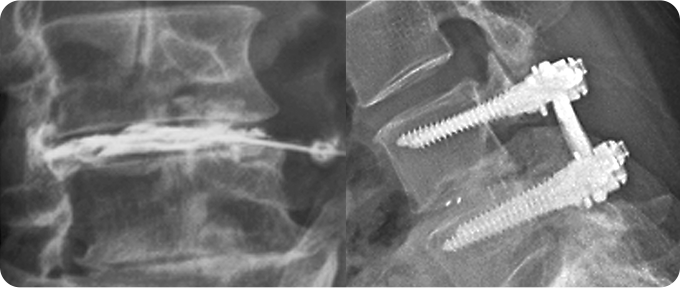

척추 감압술&고정술 사진

3

척추 감압술&고정술

신경 압박을 완화하고 척추 안정성을 확보하기 위해 사용됩니다. 척추 감압술은 골화된 후종인대를 제거하거나 척추관을 넓혀 척수 신경에 가해지는 압력을 줄이는 데 초점을 둡니다. 척추 고정술은 감압술로 인한 척추 불안정을 해결하기 위해 금속 나사 및 막대를 사용해 척추를 고정하여 안정성을 확보합니다. 두 수술은 환자의 증상 및 상태에 따라 병행될 수 있으며, 정밀한 진단과 전문의의 판단이 필수적입니다.